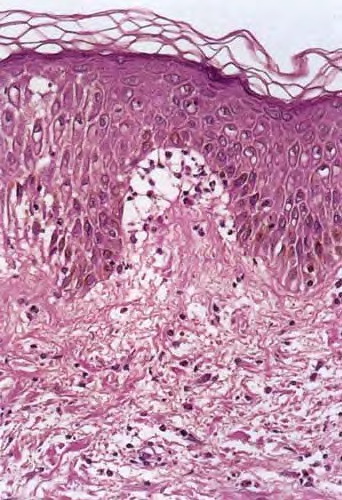

Histopathology.

In early lesions, papillary dermal edema in combination with a cell-poor or cell-rich perivascular lymphocytic and eosinophilic infiltrate is present. The blister arises at the dermal-epidermal junction . In the cell-rich pattern, which correlates clinically with blisters arising on erythematous skin , eosinophilic papillary abscesses may develop with numerous perivascular and interstitial eosinophils intermingled with lymphocytes and neutrophils in the superficial and deep dermis. Early lesions may have the histologic features of eosinophilic cellulitis (Well’s syndrome). Eosinophilic spongiosis may occur. The cell-poor pattem is observed

when blisters develop on relatively normal skin , in which there is usually a scant perivascular lymphocytic infiltrate with few eosinophils, some scattered throughout the dermis and others near the epidermis. The blister contains few inflammatory cells. Epithelial migration and regeneration may result in an intraepidermal split in older blisters. Similar to pemphigus vegetans, a hyperplasia of the epidermis, subepidermal bullae, and accumulations of eosinophils and lymphocytes may be seen.